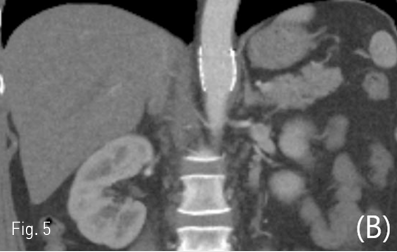

응급 지혈을 위한 스텐트-그래프트 설치술을 시행 받은 후 환자의 생체 징후는 안정화되었고, 후복강 혈종이 감소하는 양상으로 퇴원하였음. 시술 후 3개월 외래에서 시행한 경과 관찰 전산화단층활영에서 후복강의 혈종은 모두 없어졌으며 복강동맥으로의 혈류는 원활하였고 스텐트-그래프트는 상장간막동맥 바로 위에 잘 설치되었음이 확인됨(Fig. 5). 현재 3년째 외래 경과 관찰 중인 상태로 스텐트 확인을 위한 1년 주기의 전산화단층활영 검사와 정신과적 진료를 받고 있음.

Fig 5A

Follow up contrast-enhanced axial (A), coronal (B), curved MPR (C) CT scan after 3 months showed patency of celiac trunk and SMA. The ruptured pseudoaneurysm at the level of celiac trunk with hemoretroperitoneum was disappeared.

Fig 5B

Fig 5C